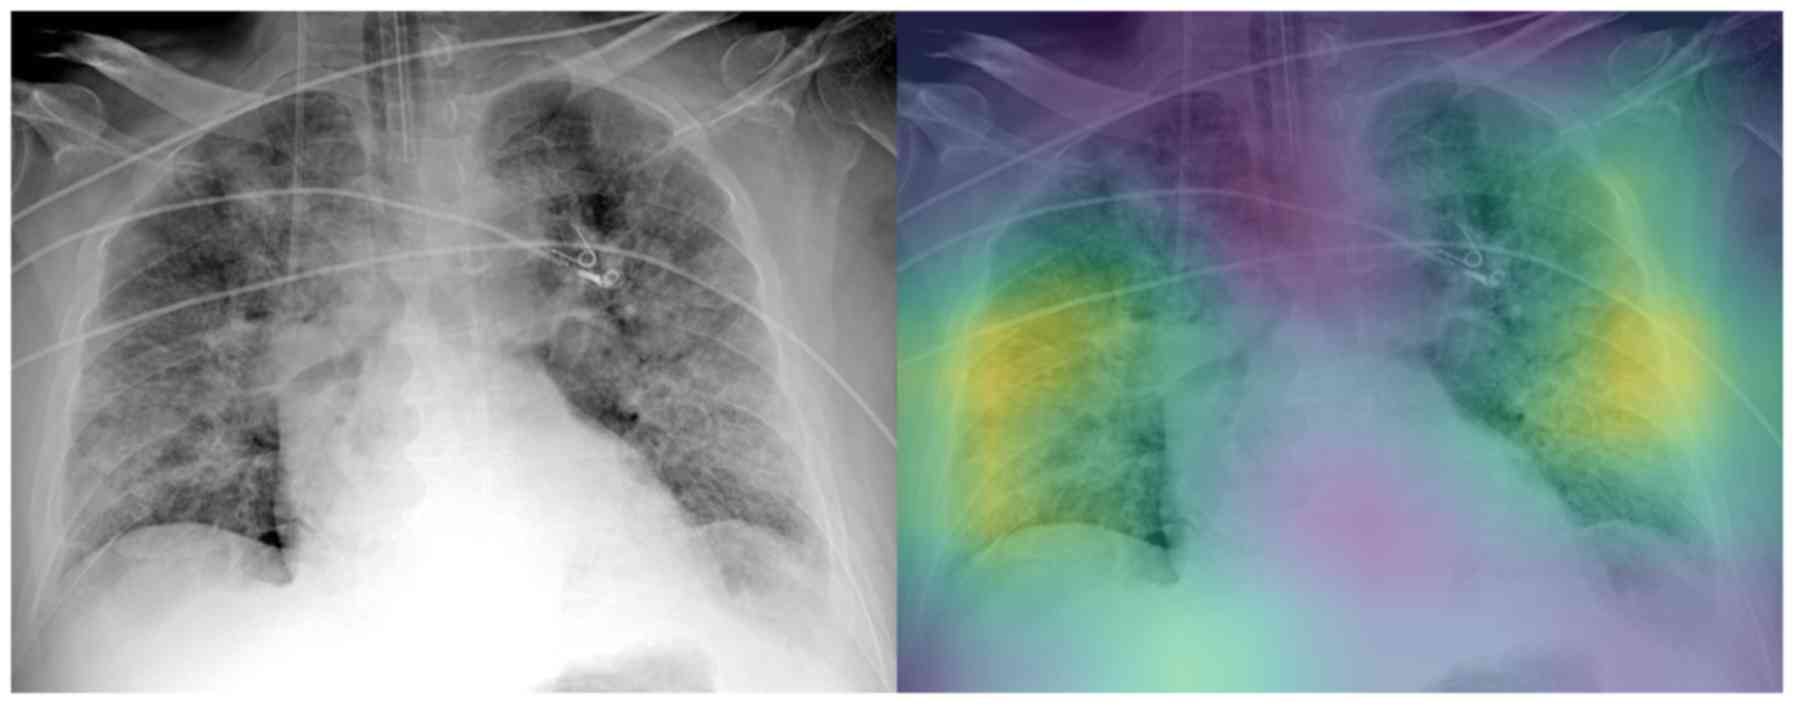

Interpretable artificial intelligence framework for COVID‑19 screening on chest X‑rays

COVID-19 has led to an unprecedented healthcare crisis with millions of infected people across the globe often pushing infrastructures, healthcare workers and entire economies beyond their limits. The scarcity of testing kits, even in developed countries, has led to extensive research efforts towards alternative solutions with high sensitivity. Chest radiological imaging paired with artificial intelligence (AI) can offer significant advantages in diagnosis of novel coronavirus infected patients. To this end, transfer learning techniques are used for overcoming the limitations emanating from the lack of relevant big datasets, enabling specialized models to converge on limited data, as in the case of X‑rays of COVID‑19 patients. In this study, we present an interpretable AI framework assessed by expert radiologists on the basis on how well the attention maps focus on the diagnostically‑relevant image regions. The proposed transfer learning methodology achieves an overall area under the curve of 1 for a binary classification problem across a 5‑fold training/testing dataset.